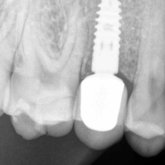

He received his Diploma in Implantology in 2016 from the University of Pretoria, which he passed with Distinction. He is also a member of the International Team for Implantology (ITI), which is based in Switzerland and offers members access to the latest research and cutting-edge techniques.

Porcelain crowns and restorations made in one appointment.

We make it a priority to incorporate the latest in dental technology in everything we do at our practice. ...